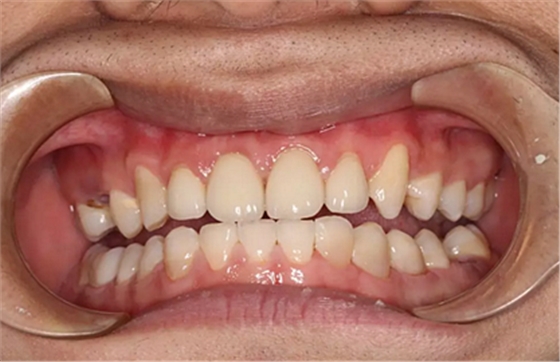

第5次復診的時候,終于讓我們4個兄弟恢復了正常的容顏。

現(xiàn)在剩下的任務就是為我其他的兄弟姐妹們治療了。需要做根管的做根管,需要做冠的做冠,需要樹脂充填的做樹脂充填。前前后后主人帶我們進行了12次的復診,歷時6個月,現(xiàn)在的我們是這樣的

再來看看曾經(jīng)的我們

經(jīng)歷了如此長久的治療,主人應該也是吸取了教訓,或許以后會改了不良的生活習慣,而我們經(jīng)歷了這段涅槃之旅,雖然也煥然一新,重塑了容顏,卻也是歷經(jīng)辛苦,如果主人能好好待我們,其實這樣的痛苦本不需要經(jīng)歷。